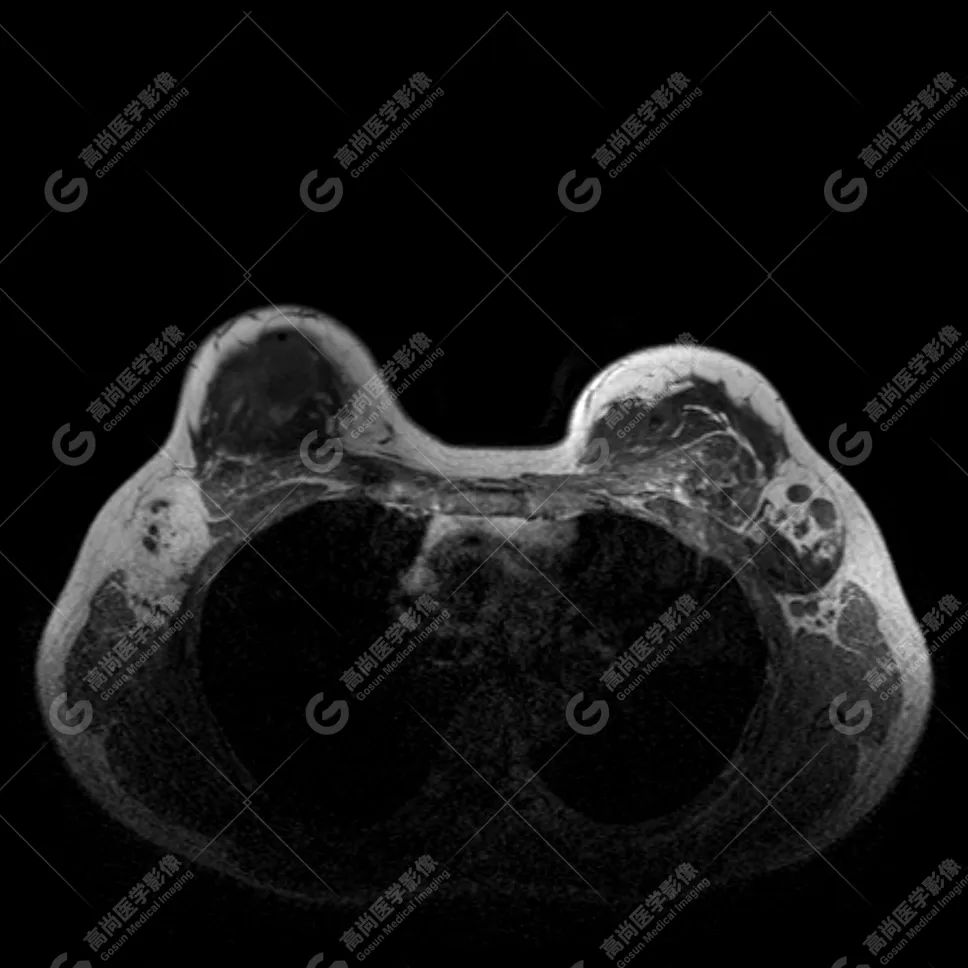

病例 1:乳腺假体植入术后 3 月余

双侧假体包膜光滑完整,内容物信号均匀。